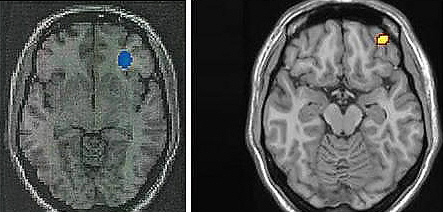

한편 지난 2009년 분당서울대병원 핵의학과 김상은 교수팀은 인터넷게임 과다 사용자의 뇌 활동<사진 우>이 마약 중독자의 뇌 활동과 유사하다는 연구결과를 발표했다. 김 교수팀은 행동성 중독으로 여겨져 온 인터넷게임 과다사용이 뇌신경학적 메커니즘으로 설명할 수 있는 ‘의학적 질환’임을 세계 처음으로 규명했다.(사진=연합뉴스)